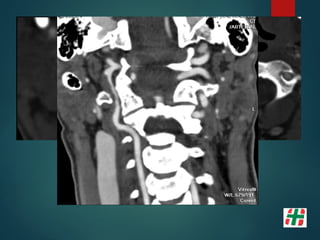

Disección Vascular

 Causa frecuente de Stroke isquémico en adultos jóvenes.

 Desgarro de la pared con formación de hematoma mural.

 Multifactorial, Trauma, infecciones, etc.

 Determinar extensión.

Mayor indicación de la secuencia TOF. Valor del crudo.

Flap de Disección

• 16.

Disección Vascular  Causafrecuente de Stroke isquémico en adultos jóvenes.  Desgarro de la pared con formación de hematoma mural.  Multifactorial, Trauma, infecciones, etc.  Determinar extensión.  Mayor indicación de la secuencia TOF. Valor del crudo.